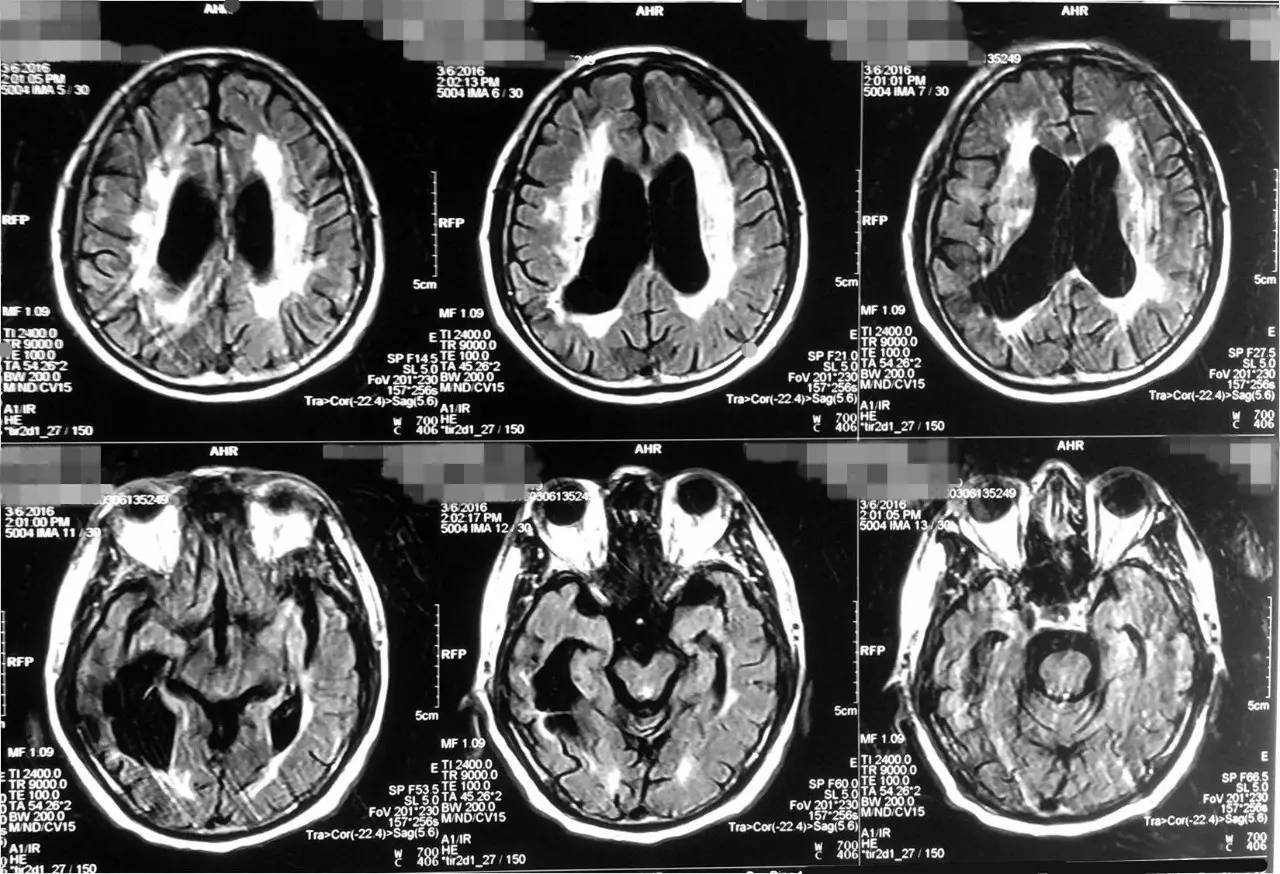

2016-3-6 头MRI+MRA示右侧基底节亚急性脑梗死;双基底节、放射冠、丘脑、脑干、右侧颞枕叶多发脑梗死,部分软化灶形成;脑萎缩改变;MRA符合动脉硬化改变。

▼头MRI(2016-3-6)

患者有无认知功能障碍,平素是否有头晕,行走不稳,尿便功能?有无逐渐加重,影像学显示患者白质病变明显,需要考虑这些问题

考虑患者是否为脑小血管病?例如CADASIL,可做基因检查